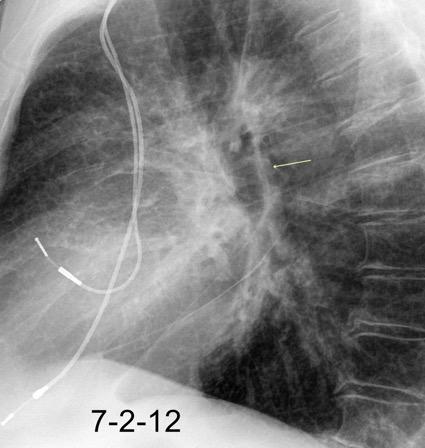

Hematoma retroesternal y pericárdico en cirugía de válvula mitral. Migración de suturas

Boiselle P.M.et al. Wandering wires: frequency of sternal wire abnormalities in patients with sternal dehiscence. AJR 1999;